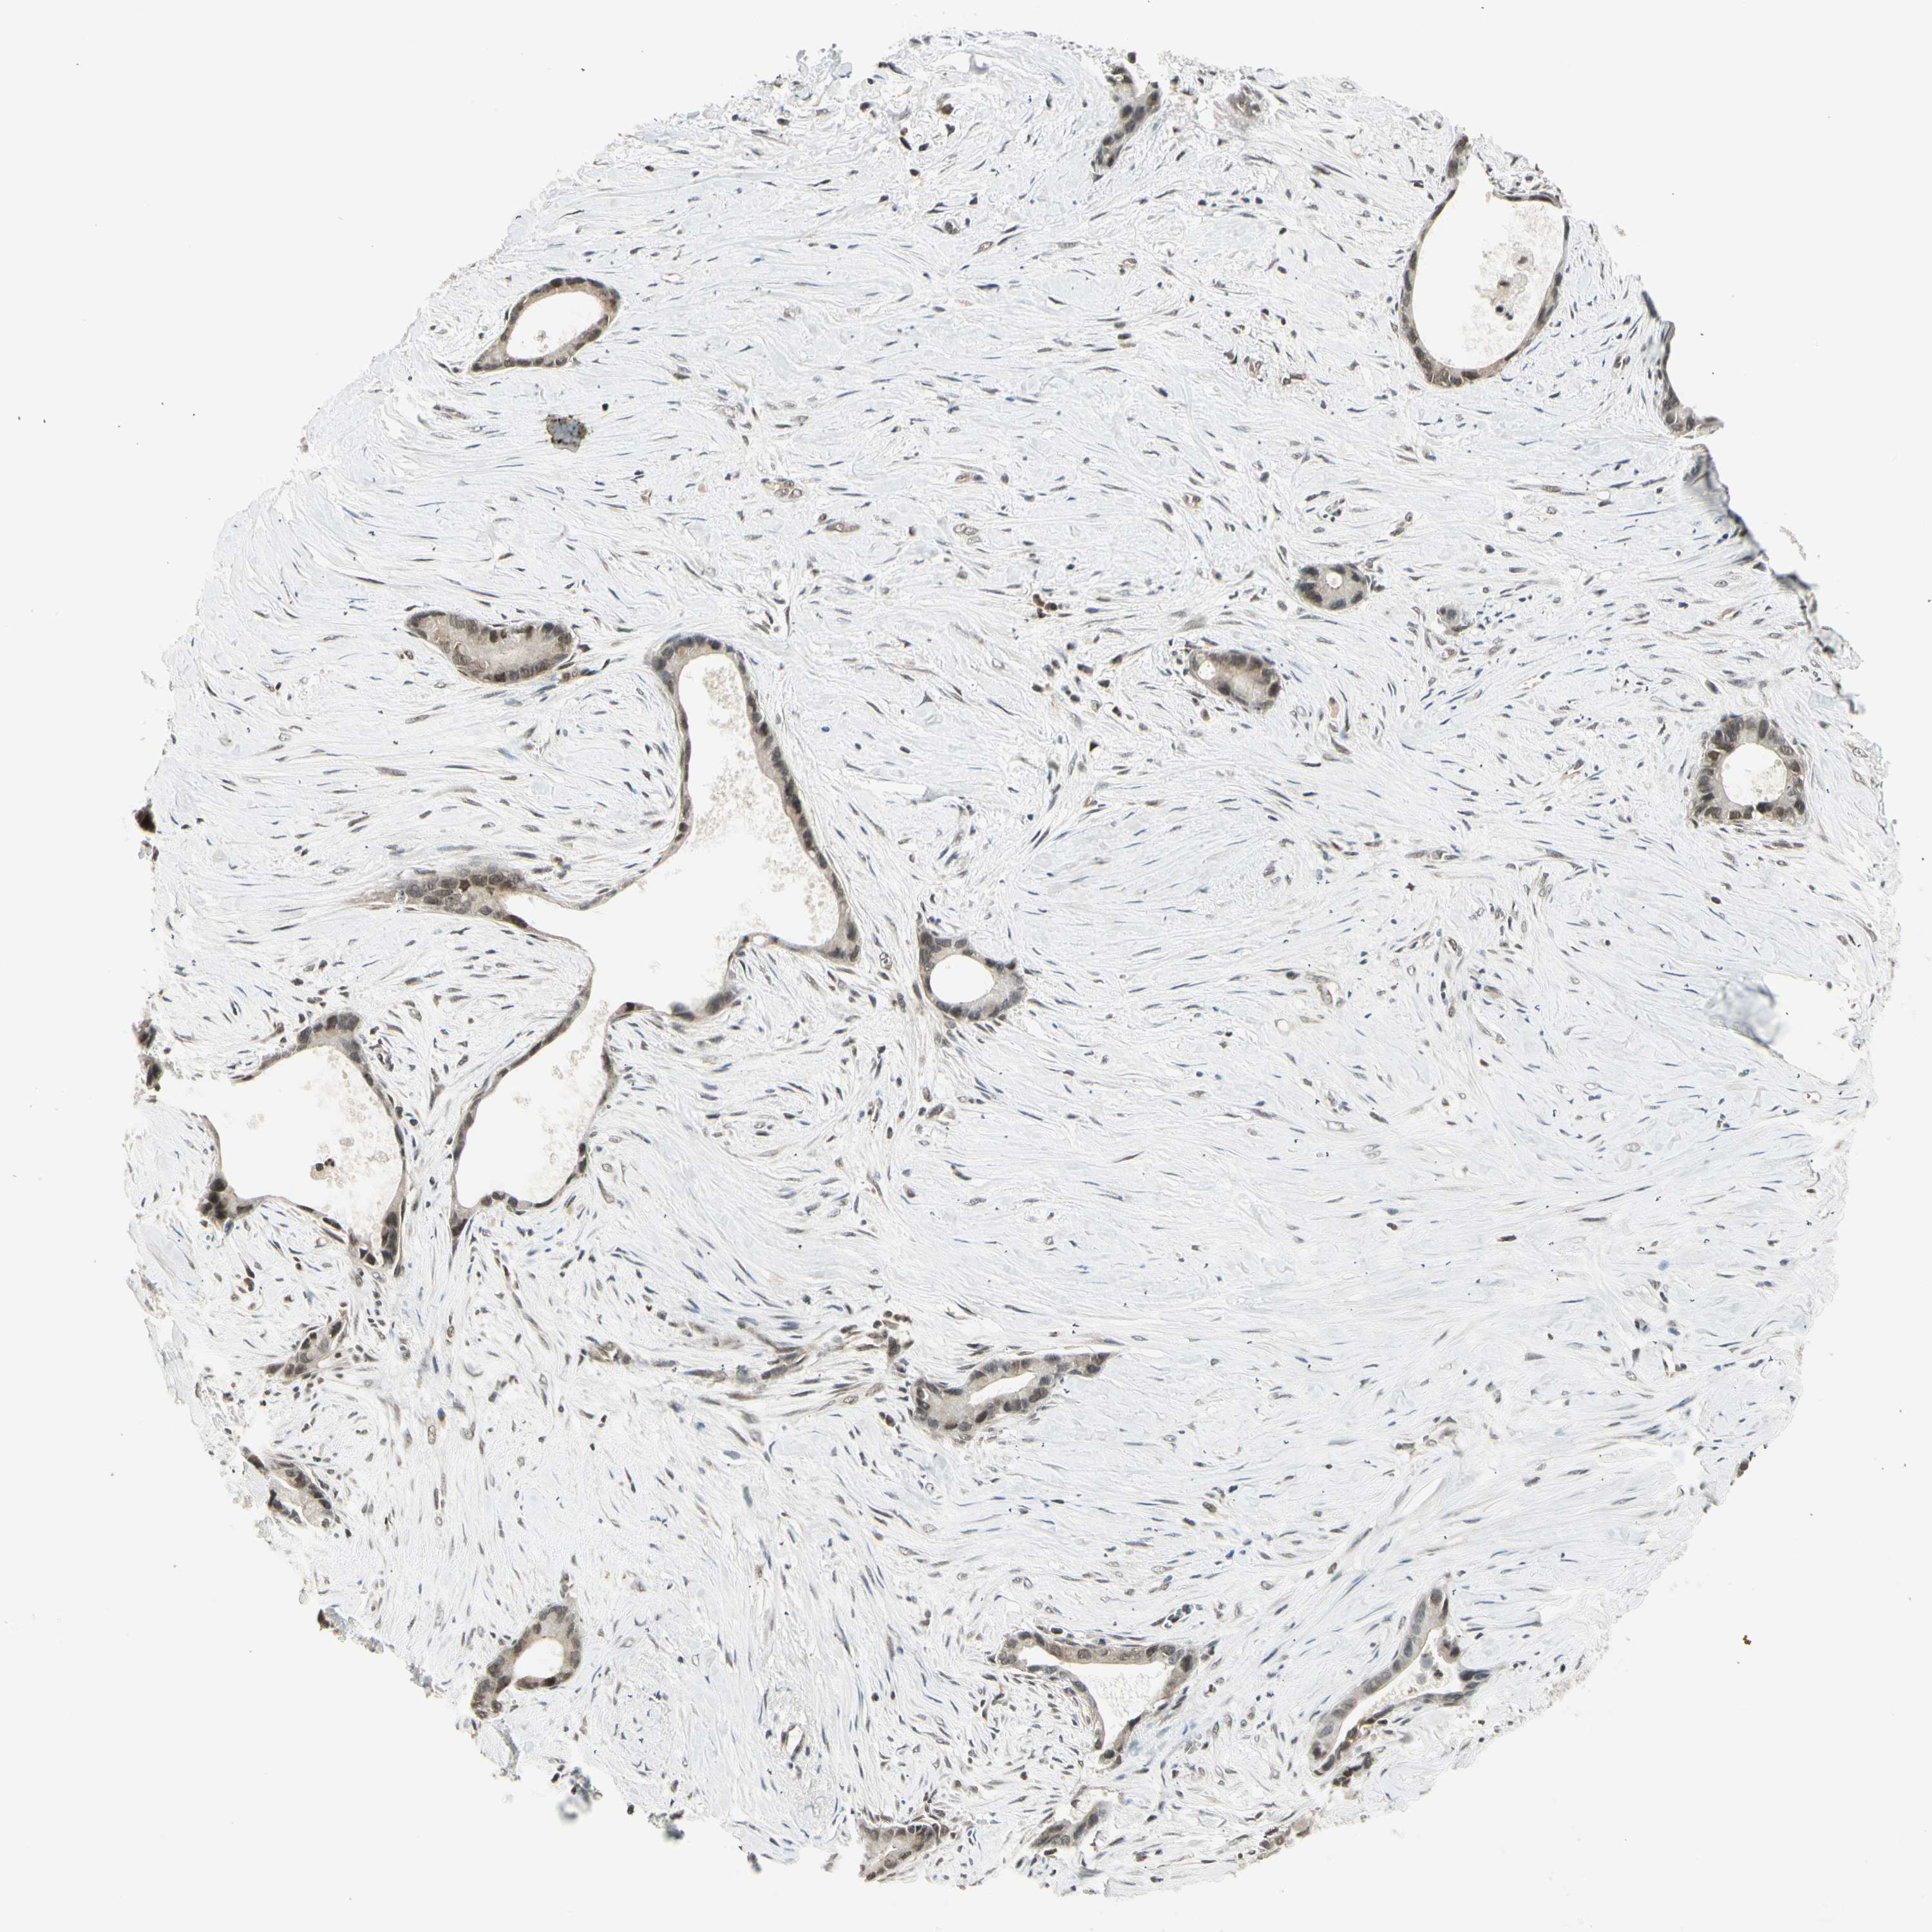

LIVER CANCER - Protein expressioni

A mouse-over function shows sample information and annotation data. Click on an image to view it in a full screen mode. Samples can be filtered based on level of antibody staining by selecting one or several of the following categories: high, medium, low and not detected. The assay and annotation is described here.

Note that samples used for immunohistochemistry by the Human Protein Atlas do not correspond to samples in the TCGA dataset.

Antibody stainingi

Antibody staining in the annotated cell types in the current human tissue is reported as not detected, low, medium, or high, based on conventional immunohistochemistry profiling in selected tissues. This score is based on the combination of the staining intensity and fraction of stained cells.

Each image is clickable and will lead to virtual microscopy that enables deeper exploration of all samples and also displays staining intensity scores, fraction scores and subcellular localization as well as patient and tissue information for each sample.

Antibody HPA045271

Antibody CAB009344

Staining

High

Medium

Low

Not detected

Intensity

Strong

Moderate

Weak

Negative

Quantity

>75%

75%-25%

<25%

None

Location

Nuclear

Cytoplasmic/membranous

Cytoplasmic/membranous,nuclear

Cholangiocarcinoma

Carcinoma, Hepatocellular, NOS